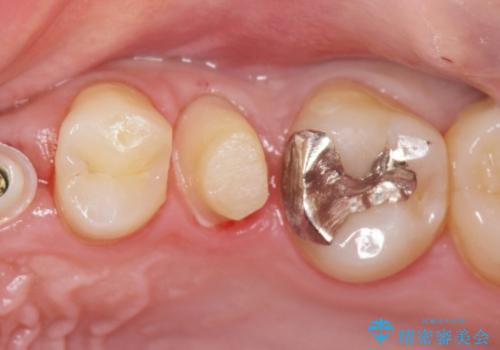

- ねじれてしまっている奥歯の矯正治療、銀歯のセラミック治療を求めて来院されました。

銀歯を外す前に部分矯正治療を行うことで歯のポジションを調整したのち、セラミック治療を行います。

90°ねじれてしまっていた歯を、矯正治療で治し、前後の歯の咬合関係も改善してしっかりと噛めるようになりました。